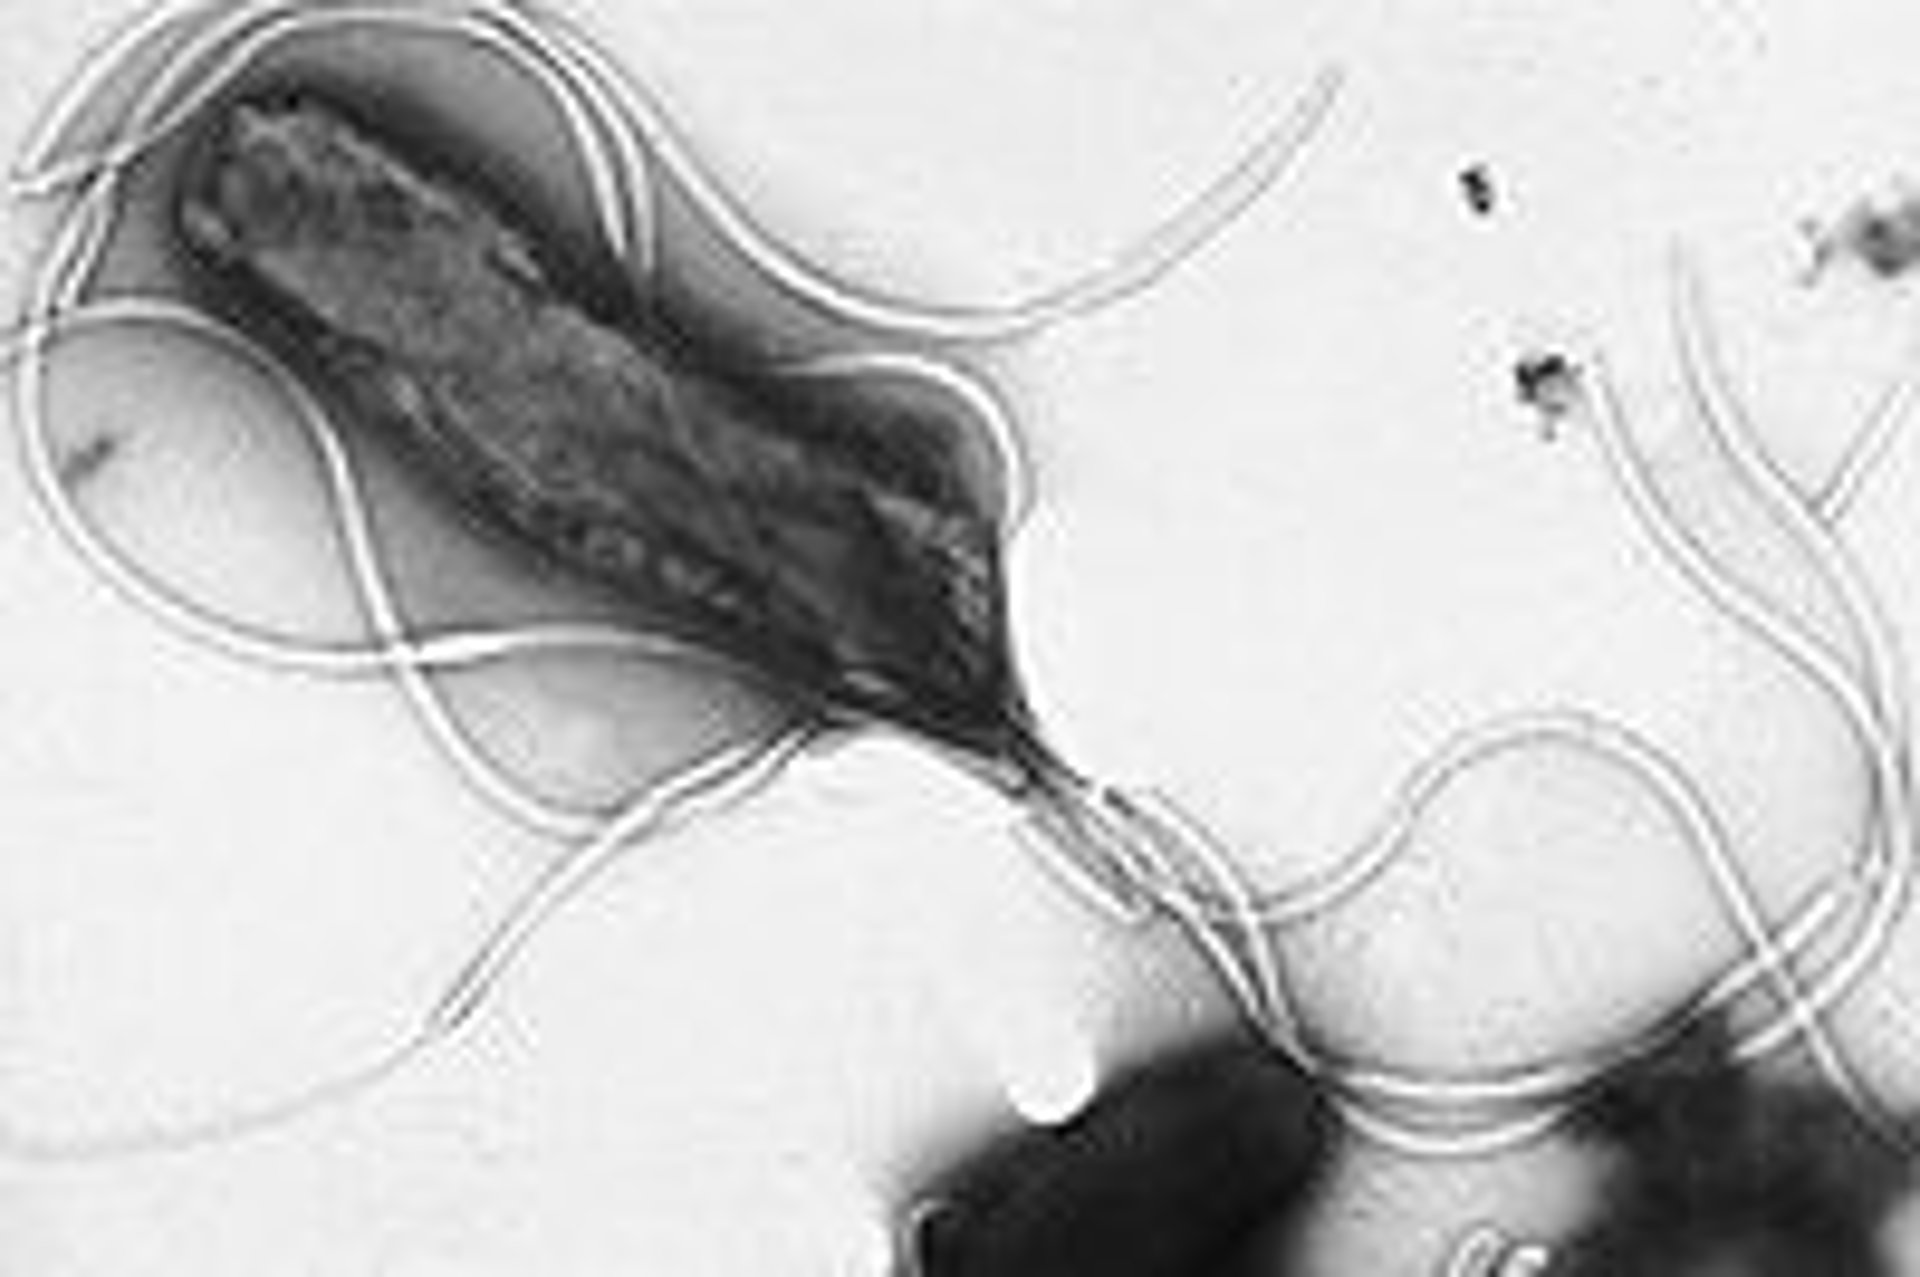

'Helicobacter pylori'

WIKIPEDIA

Investigadores del Instituto Catalán de Oncología (ICO) y del Instituto de Investigación Biomédica de Bellvitge (Idibell) han identificado a los pacientes con riesgo más elevado de sufrir un cáncer gástrico, provocado por la variante más agresiva de la bacteria 'Helicobacter pylori', que puede desencadenar un tumor tras 15 ó 25 años en el estómago.

Según González Svatetz, esta infección es "una de las más comunes en el mundo, y siempre ha estado en el estómago del ser humano por razones desconocidas", y también se desconocen los mecanismos de transmisión.